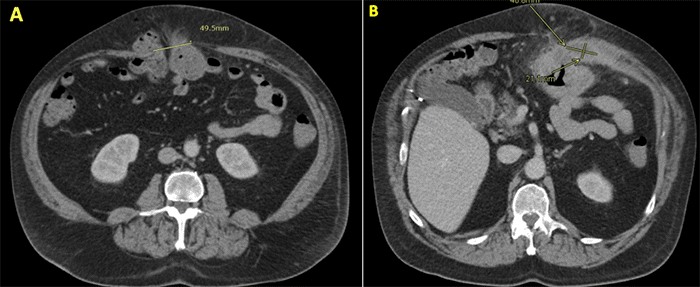

Over the subsequent years, the patient did not undergo elective surgical repair of the ventral hernia as he was unable to meet his surgeon’s preoperative medical optimization criteria. In June 2023, his condition acutely worsened, prompting presentation to a local hospital with a two-week history of escalating abdominal pain and new-onset erythematous skin changes overlying the longstanding hernia. His review of systems was positive for rust-colored stools but otherwise negative. On admission, he was febrile to 39.4°C with a heart rate of 99 bpm. His abdominal examination was described as benign, without signs of generalized peritonitis despite the systemic signs of infection. A CT scan demonstrated a colonic mass within the known ventral hernia sac, which appeared to be perforating directly into the abdominal wall musculature (Figure 2A), complicated by a superimposed abdominal wall abscess (Figure 2B). There were no CT findings suggestive of acute bowel ischemia or distant metastatic disease. Intravenous antibiotics were initiated for the cellulitis and underlying abscess, leading to clinical improvement.

Figure 2. CT Findings at Acute Presentation (June 2023). Published with Permission

(A) Axial view depicting the large ventral hernia (hernia defect measuring approximately 49.5 mm in this image) containing a significant colonic mass (arrow) with evidence of invasion through the fascial defect into the abdominal wall. (B) Axial view demonstrating an associated complex fluid collection within the abdominal wall soft tissues (arrow), measuring approximately 40.8 × 21.1 mm, consistent with an abscess and surrounding inflammatory fat stranding.